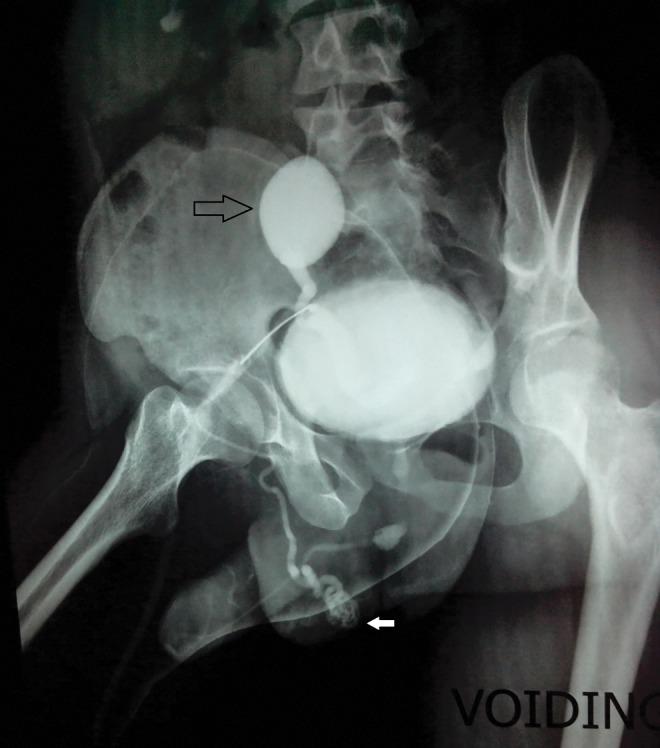

A 24-year-old male presented with voiding lower urinary tract symptoms. On evaluation, the patient was found to have midbulbar urethral stricture and right dysplastic pelvic kidney with right vesicoureteral reflux. A micturating cystourethrogram (MCUG) shows opacification of the right vas deferens along the entire course till the testis. The patient underwent end-to-end urethroplasty. But soon the patient presented with urinary tract infection (UTI) and epididymorchitis in the follow-up period. The patient was explored laparoscopically to remove dysplastic kidney and ectopic vas deferens. Laparoscopically, the testicular end of the left vas deferens entering the deep inguinal ring was clipped and cut. Also the dysplastic kidney and ureter were removed till the vesicoureteral junction. At 1 year of follow-up, the patient is voiding well with no episodes of UTI.

一名24岁男性出现下尿路排尿症状。经评估,发现该患者患有球部中段尿道狭窄以及右肾发育异常伴右侧膀胱输尿管反流。排尿性膀胱尿道造影(MCUG)显示右侧输精管全程直至睾丸均显影。该患者接受了端端尿道成形术。但在随访期间,患者很快出现了尿路感染(UTI)和附睾炎。对患者进行腹腔镜探查以切除发育异常的肾脏和异位输精管。在腹腔镜下,夹闭并切断进入深腹股沟环的左侧输精管的睾丸端。同时将发育异常的肾脏和输尿管切除至膀胱输尿管连接处。随访1年时,患者排尿良好,未出现尿路感染发作。